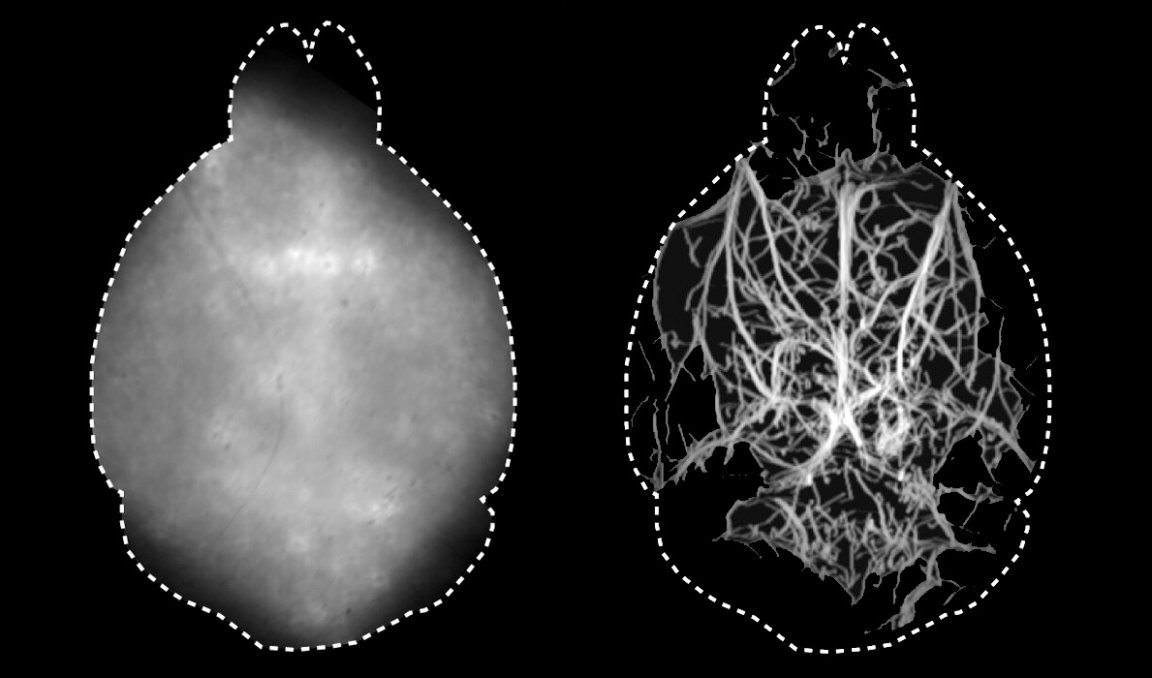

The new technique does away with all of that, according to research published Thursday in the journal Optica, and produces a detailed and dynamic map of the brain’s vasculature that researchers say could be a valuable medical tool.

Specifically, Razansky and his team injected the mice with fluorescent microdroplets that traveled throughout their circulatory system and used a specific wavelength of infrared light that can better penetrate bone to illuminate them, according to the study. It’s a similar concept to an fMRI scan in that it allows scientists to peer inside the brain and see which regions are active and when, except this is the first time that scientists have been able to do so using fluorescent microscopy.